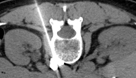

Im Zentrum für Wirbelsäulenchirurgie und Schmerztherapie wird das gesamte Behandlungsspektrum bei Erkrankungen, Unfällen und Schmerzsyndromen der Hals-, Brust- und Lendenwirbelsäule sowie der angrenzenden Strukturen bei Kindern und Erwachsenen in interdisziplinärer Vorgehensweise abgedeckt. Rund um die Uhr besteht die Möglichkeit der Maximalversorgung. Häufig erfolgt die Therapie nach einem Stufenschema, bei dem versucht wird, mit weniger eingreifenden Maßnahmen zu beginnen. Je eingreifender die Therapie, umso höher ein theoretisches Risiko des Auftretens negativer Nebeneffekte.

Insgesamt steht die Behandlung von Verschleißerkrankungen im Vordergrund. Des Weiteren werden im Zentrum jegliche Arten von z. B. Unfällen, Infektionen, Tumoren und Metastasen, Deformitäten, rheumatischen und angeborenen Erkrankungen bei Erwachsenen und Kindern behandelt. Jährlich erfolgen neben den konservativen mehr als 15.000 interventionelle Maßnahmen sowie mehr als 3.000 Operationen. Wenn möglich werden minimalinvasive oder bewegungserhaltende Verfahren angewendet.